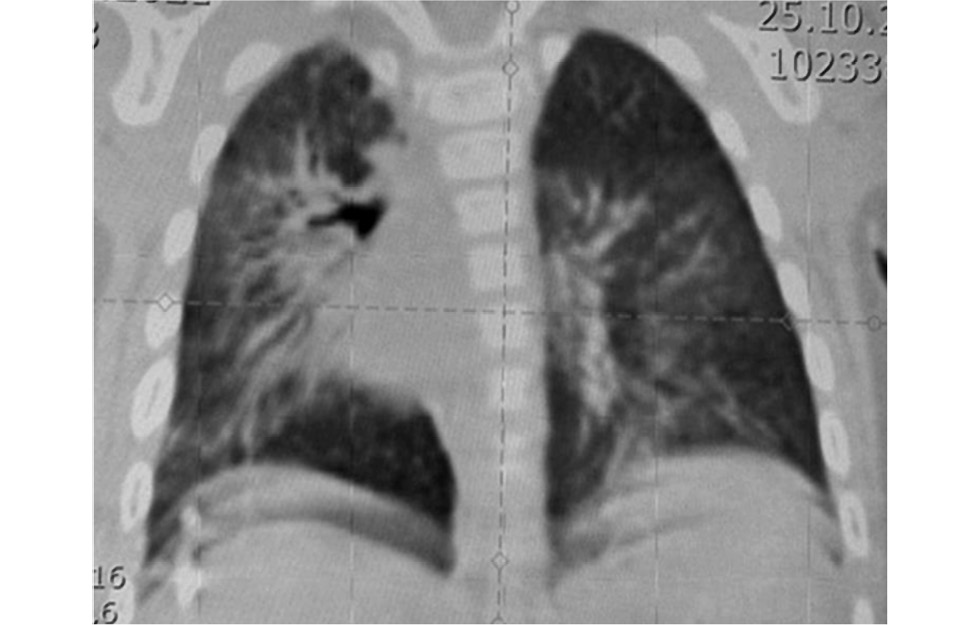

Состояние ребёнка в этот период было относительно стабильным — проводилась вспомогательная ИВЛ с преимущественным участием пациента в акте дыхания, концентрация кислорода в газовой смеси снизилась до 30%. Больная экстубирована в возрасте 1 мес. 26 дней и на полном энтеральном питании переведена в отделение патологии новорождённых с минимальной респираторной поддержкой через кислородную воронку. Однако при повторной БС выявлена гиперплазия слизистой правого главного бронха с субтотальной обструкцией просвета. При дыхании отмечалась асимметрия и снижение экскурсии правой половины грудной клетки, при этом ДН не прогрессировала. В этот период в состоянии ребёнка на первый план вышли неврологические и офтальмологические проблемы: нарастала окклюзионная гидроцефалия, что потребовало срочного этапного нейрохирургического лечения; прогрессировала ретинопатия. В возрасте 4,5 мес. при БС выявлен фиброзный стеноз правого главного бронха. По МСКТА органов грудной полости — сохранялся ТАПЛ (рис. 7).

Рис. 7. Мультиспиральная компьютерная томография-ангиография органов грудной полости на 4,5 мес. жизни: сохраняется тотальный ателектаз правого лёгкого (a — аксиальная реконструкция, b — фронтальная реконструкция; c — сагиттальная реконструкция).

Fig. 7. Multispiral computed tomography-angiography of the chest organs at 4.5 months of life: total atelectasis of the right lung persists (a — axial reconstruction, b — frontal reconstruction; c — sagittal reconstruction).